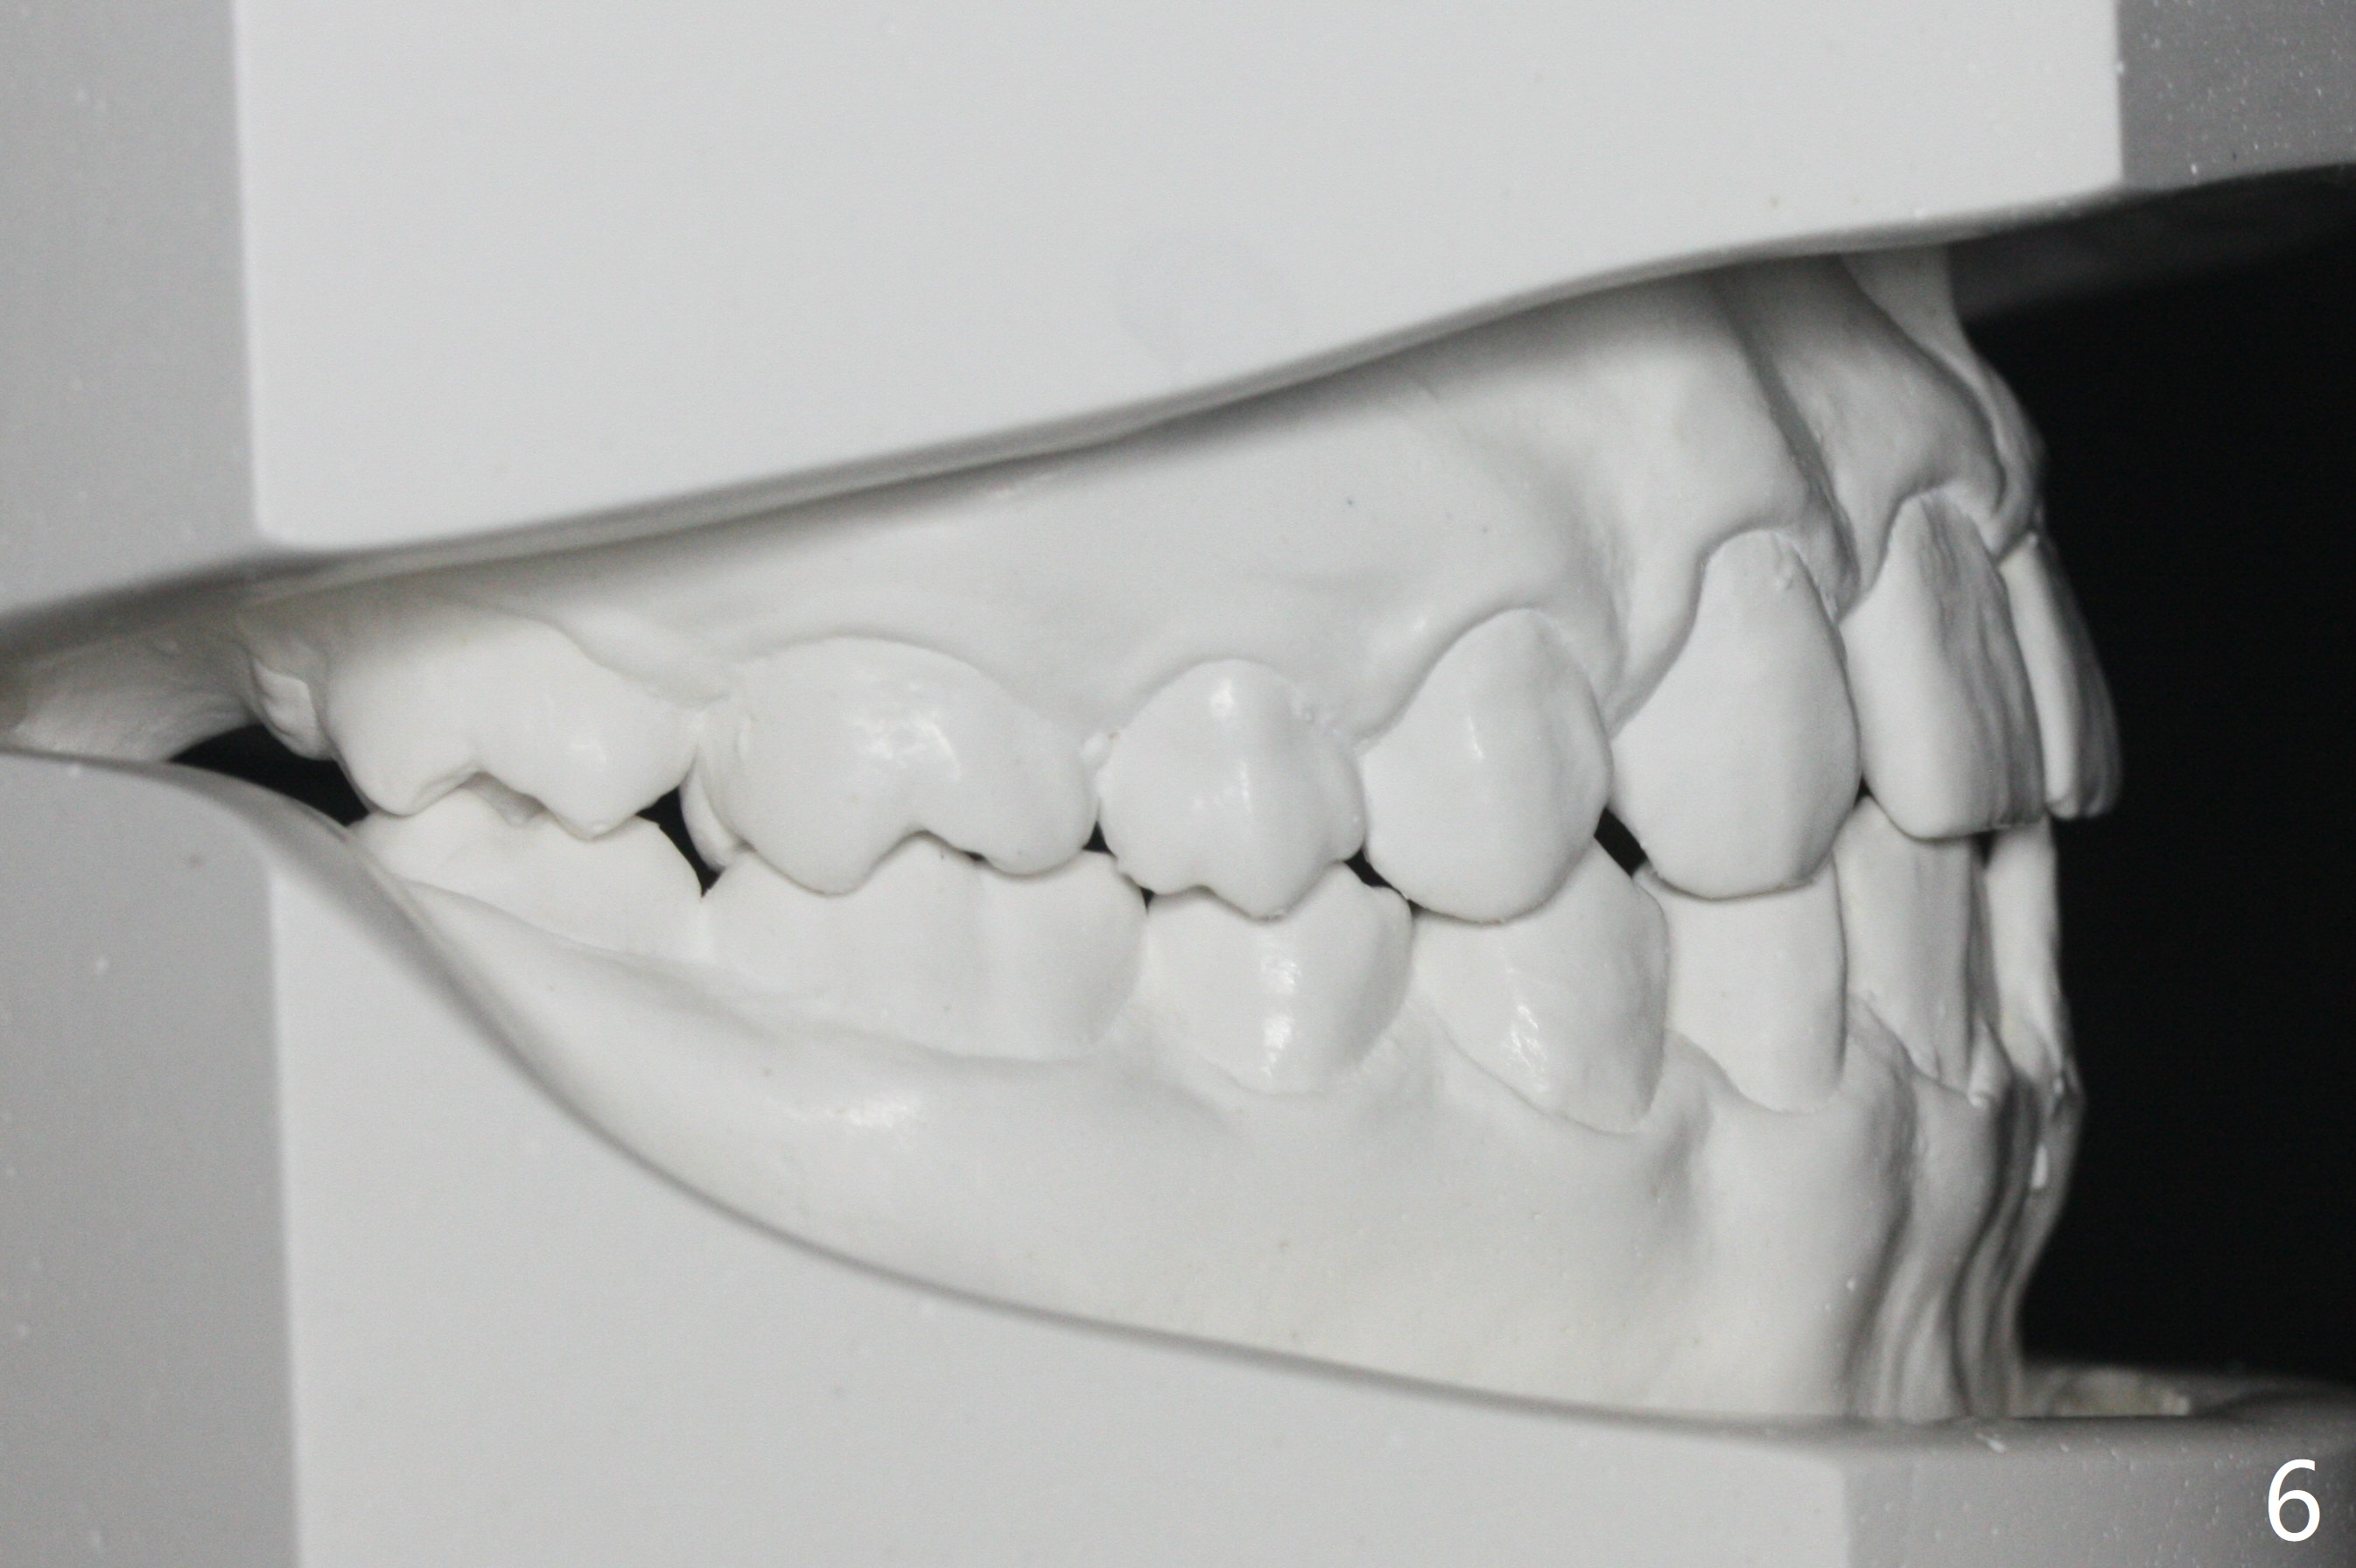

A 14-year-old man requests ortho because of crowding lower anterior and UR missing lateral (Fig.1-4). Open space for the future implant at UR2 will correct upper midline deviation (Fig.1) and change Class II malocclusion to I on the right (Fig.6, as compared to Fig.7). To control UR1,3 root torque, bracketing on these 2 teeth will be intentionally off (Fig.5). The treatment will take ~ 2 years. Prior to implantation at UR2, what type of prosthesis should be made?